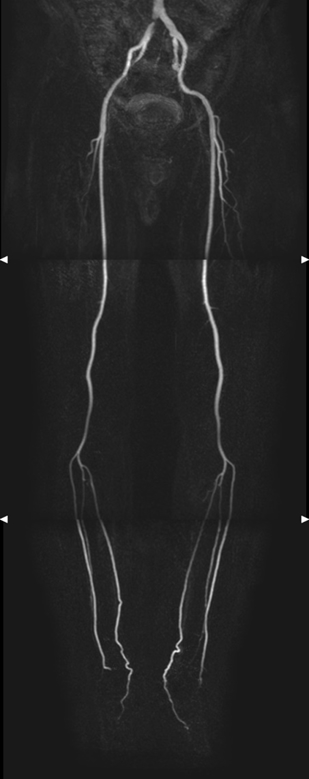

非造影血管MRI検査

下肢の動脈が詰まる閉塞性動脈硬化症などの動脈硬化性疾患を造影剤を使用せずに撮像することができます。

下肢血管造影検査

下肢血管造影検査は、下肢に行く血管にカテーテルを進め、カテーテルから造影剤を注入して撮影することで、下肢の動脈が狭くなっていないかなどを観察する検査です。

下肢の血管が狭い場合には、バルーンと呼ばれる風船状のカテーテルで血管を拡げたり、ステントと呼ばれる金網の筒で血管を補強する経皮的血管形成術とよばれる治療を行います。